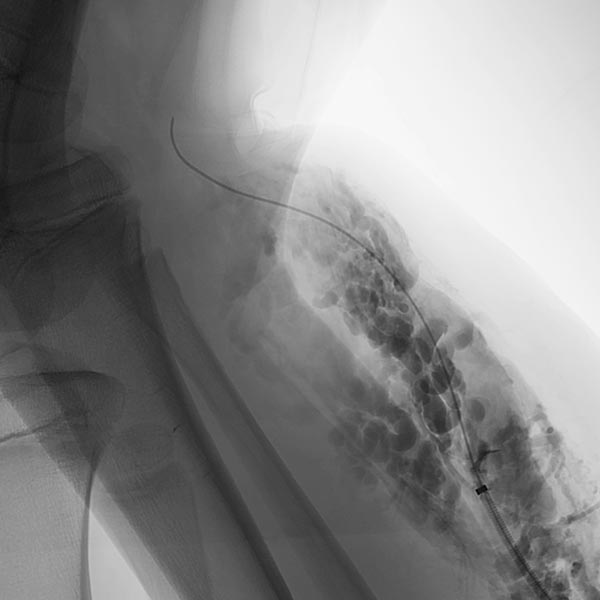

Phlebography after direct puncture of the venous malformation shows a large-lumen drainage vein communicating with the popliteal vein in the popliteal fossa. This must be occluded before sclerotherapy, otherwise the sclerosing agent could unintentionally dislocate through this communication and potentially cause thrombosis of the deep venous system of the leg and/or pulmonary embolism. In addition, there is an ongoing, increased risk of thromboembolism in this patient even outside of sclerotherapy, which can be significantly reduced by occlusion of the communication.

To occlude the vein, a large-lumen introducer sheath is first advanced via a guidewire. This sheath is used to insert the laser fiber and is advanced via the vein to the communication point in the popliteal fossa.

A laser fiber is advanced through this sheath for endovascular laser therapy. The heat of the laser beam causes massive irritation of the vein wall, which subsequently closes quickly. Thrombus formation immediately occurs around the laser tip.

After occlusion via laser fiber and contrast injection via the pulled-back introducer sheath, there is no more outflow of the contrast medium via the communicating vein. Thus the communication is successfully occluded. Only the venous malformation is still contrasted. This is now ready for sclerotherapy, as the sclerosing agent can no longer drain into the deep venous system of the leg.